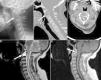

A 43-year-old, previously healthy woman presented with a sharp pain in the occipital and cervical regions with associated paresthesias in suboccipital and left retroauricular region (C2-C3 dermatomes). It had begun 9 months earlier. She was treated with analgesics, muscle relaxants and transcutaneous electrostimulation, but had noticed no improvement. Physical examination found an overall limitation to her cervical mobility and hypoesthesia in left C2-C3 dermatomes. The laboratory tests, including a complete blood count, biochemistry, acute-phase reactants (erythrocyte sedimentation rate [ESR] was 12mm/h, her C-reactive protein [CRP] 3.78mg/L), bone metabolism (Ca 8.7mg/dL, P 3.2mg/dL, 25 OH-vitamin D 39ng/mL and parathyroid hormone 44pg/mL) were normal. Lateral radiograph of the cervical spine (Fig. 1A) revealed the presence of an expansile lytic lesion occupying the C2 vertebral body. Computed tomography (CT) confirmed that the lesion totally replaced the bone marrow and interrupted the cortical (Fig. 1B and C). The lesion was hyperintense, the T2-weighted sequence of magnetic resonance imaging (MRI) reduced the caliber of the 2 holes linking C2-C3, showing areas of necrosis, fluid-fluid levels and peripheral enhancement (Fig. 1D and E). The patient was subjected to C1-C2-C3 arthrodesis due to the cervical instability caused by the lesion, which was removed using a transpharyngeal route and the defect was filled with demineralized bone matrix. The histopathological study showed a proliferation of mono- and multinucleated cells with no nuclear atypia, frequent cavities full of red cells and foci of bone neoformation and osteoid deposition. These findings were consistent with GCT or an aneurysmal bone cyst (ABC). The pain and paresthesias improved after the procedure, but these symptoms became worse 8 months later. Radiograph and CT showed recurrence of the lesion, this time with associated retropharyngeal mass. Surgery was repeated to remove the C2 using a translabiomandibular approach and occipitocervical fusion. Histopathology confirmed that the lesion was a GCT with extensions to neighboring soft tissue (Fig. 2). The patient recovered satisfactorily after the procedure, and has had no recurrences or complications after a follow-up period of 21 months.

Lateral radiograph of the cervical spine (A) showing an expansile osteolytic lesion in the vertebral body of C2 with cortical insufflation (arrow). Sagittal (B) and axial (C) planes in cervical spinal computed tomography showing that the lesion totally replaced the bone marrow (arrow) and interrupted the cortical at the right posterolateral surface of the vertebral body (arrow). Sagittal view in T2-weighted sequences (D) and in T1 after gadolinium enhancement (E) in magnetic resonance imaging of the cervical spine, which showed a cystic area, necrosis and trabeculation. The lesion was markedly hyperintense in T2 and hypointense in T1, showing peripheral enhancement after the administration of gadolinium (arrows).